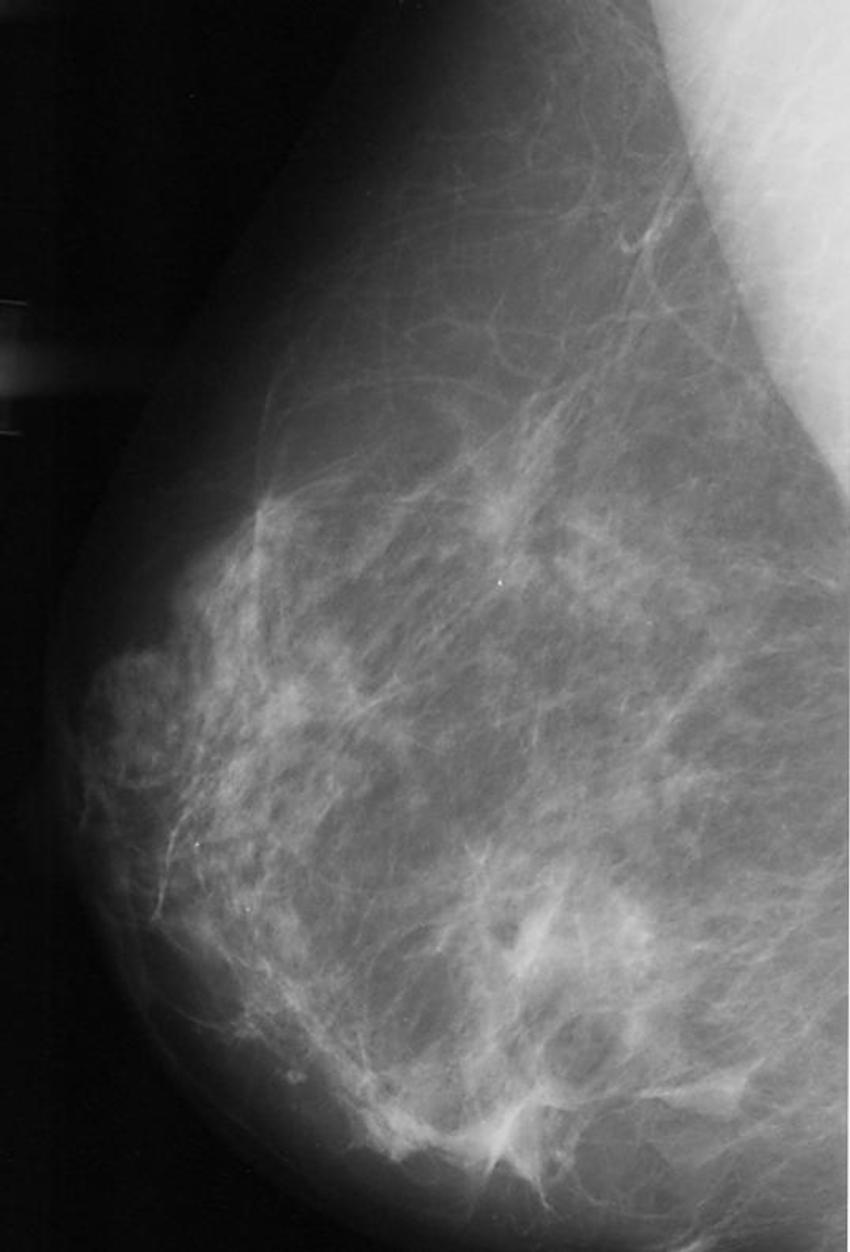

Figure 2. Abnormal mammogram.

High-res (TIF) version

Figure 3. Normal mammogram.